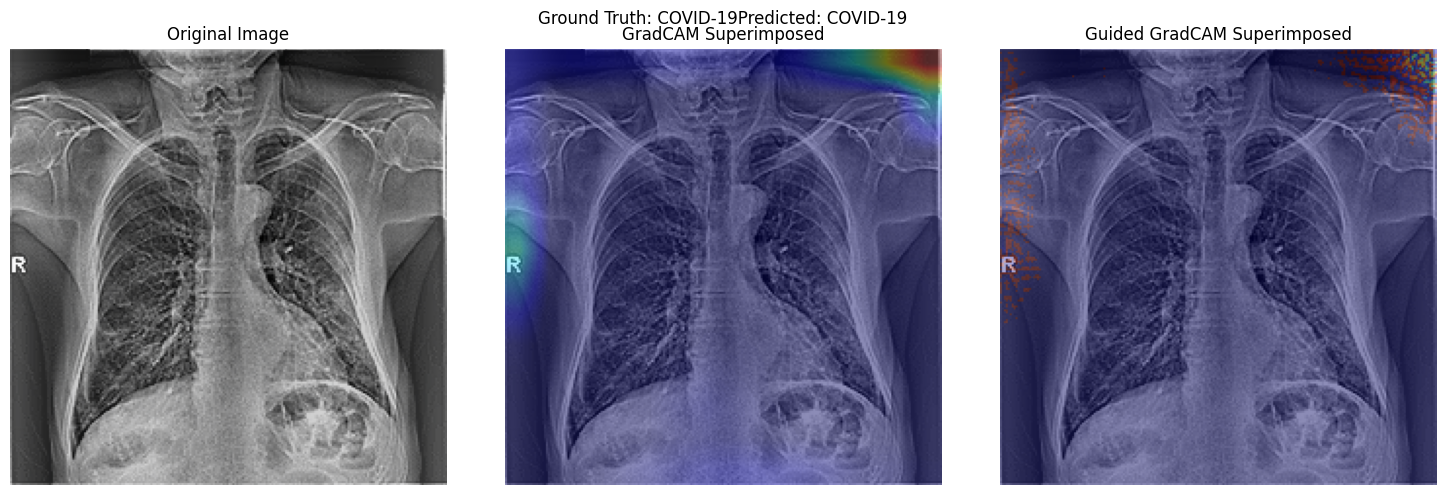

Gradient activation and attention map visualisation for Model Interpretability.

VGG19 Activation Visualisation Using Grad Cam and Guided Grad Cam.

Activation Map Visualisation

Research Question 2 and Model Interpretability.

• Research Question 2 : What insights can be derived from activation visualization or attention map visualization about the decision-making process of the pre-trained vgg19, resnet50 models or custom CNN and vision transformer models, respectively, in predicting respiratory diseases from chest radiological images?

• Insights from Activation and Attention Map Visualizations in Chest Radiological Images Classification

• Activation and attention map visualizations offer transparency into neural networks, highlighting areas deemed significant during predictions. Such insights are crucial for medical imaging applications, where the understanding of a model's focus can aid in validation and trust.

• 2. VGG19:

Gradient visualizations for VGG19 revealed its attention predominantly on image noise and artifacts, potentially due to the absence of a zoom preprocessing step. This highlights the importance of diligent preprocessing in medical imaging.